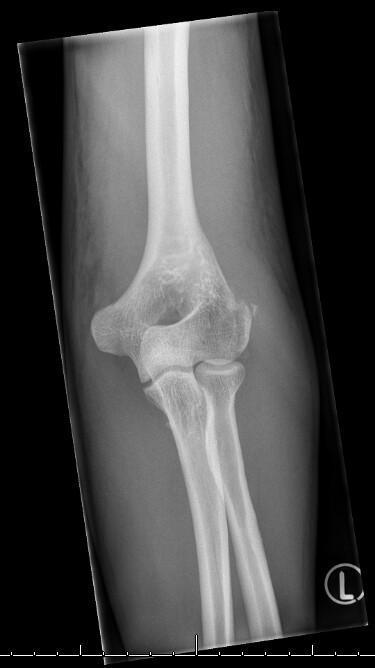

Chitani Mbewe, Radiopaedia.org. From the case rID: 78402

Comprend fracture de l’extrémité distale de l’humérus, fracture de l’olécrâne, fractures des extrémités proximales du radius et ulna.

Avis chirurgical.

Devant une fracture du coude, examiner systématiquement le poignet ++.